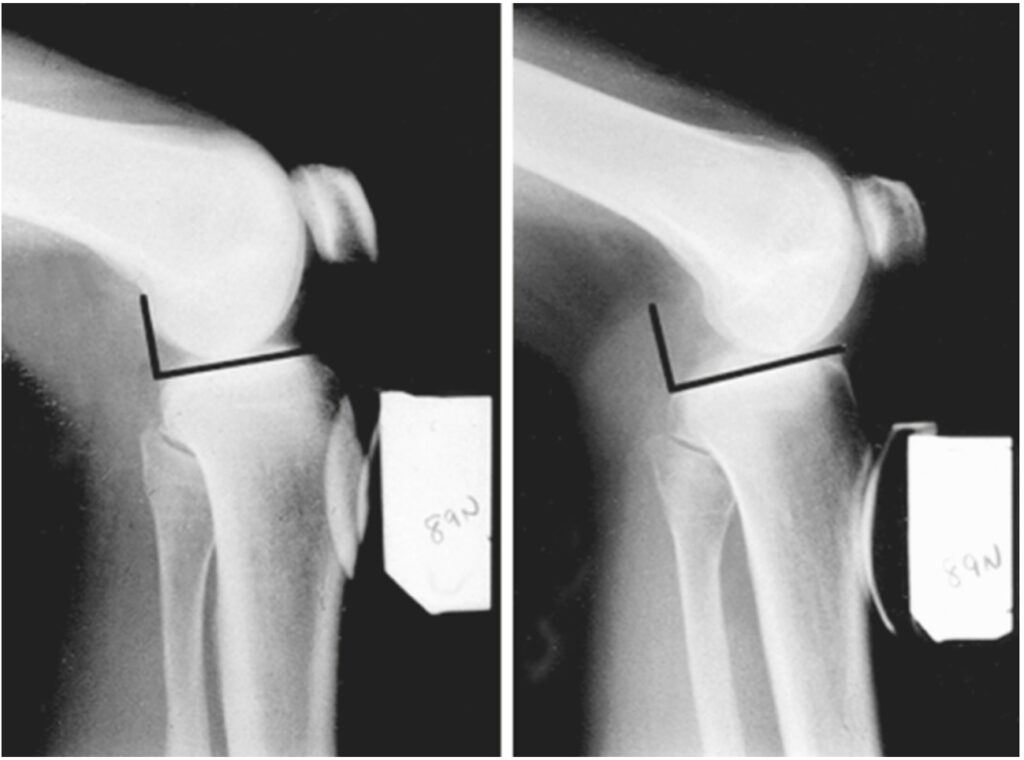

Entres os exames destacam-se a radiografia sob estresse e a ressonância magnética.